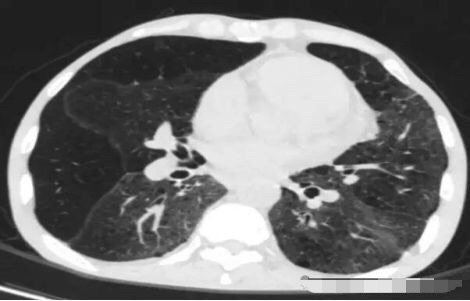

请问王大夫,这个那么像磨砂玻璃,这种是肺癌吗?

不是的,这个是肺泡蛋白沉积症,患者的肺像铺路石一样。